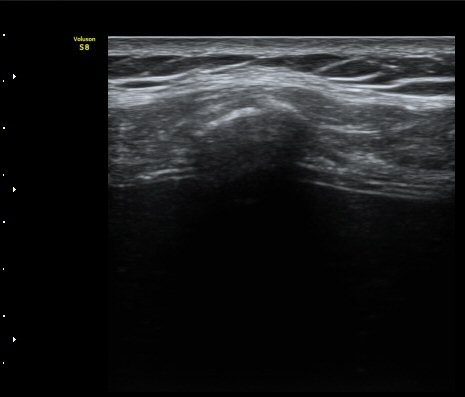

°¥ºñ»À Ⱦ´Ü¸é°Ë»ç¿¡¼­ °¡°ñ Çü¼ºÀÌ °üÂûµÊ(formation of callus)   »çÁø 4

°ñ À¯ÇÕÀÌ È®ÀεÊ.